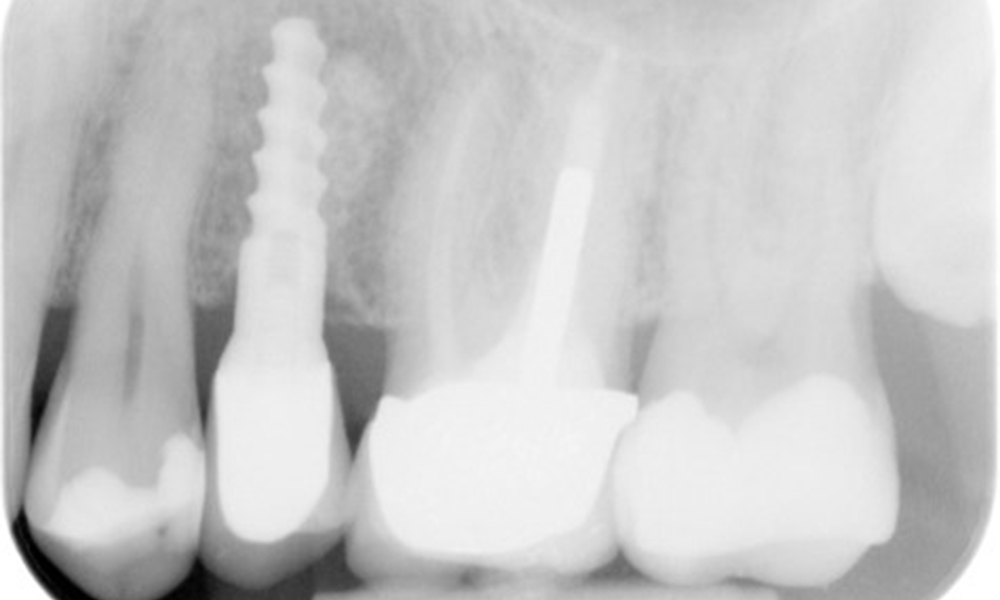

The X-ray image shows the bone loss

The X-ray images show the bone loss.

X-ray images (or bitewing X-rays)

X-ray images (or bitewing X-rays) taken on: 18/02/2021